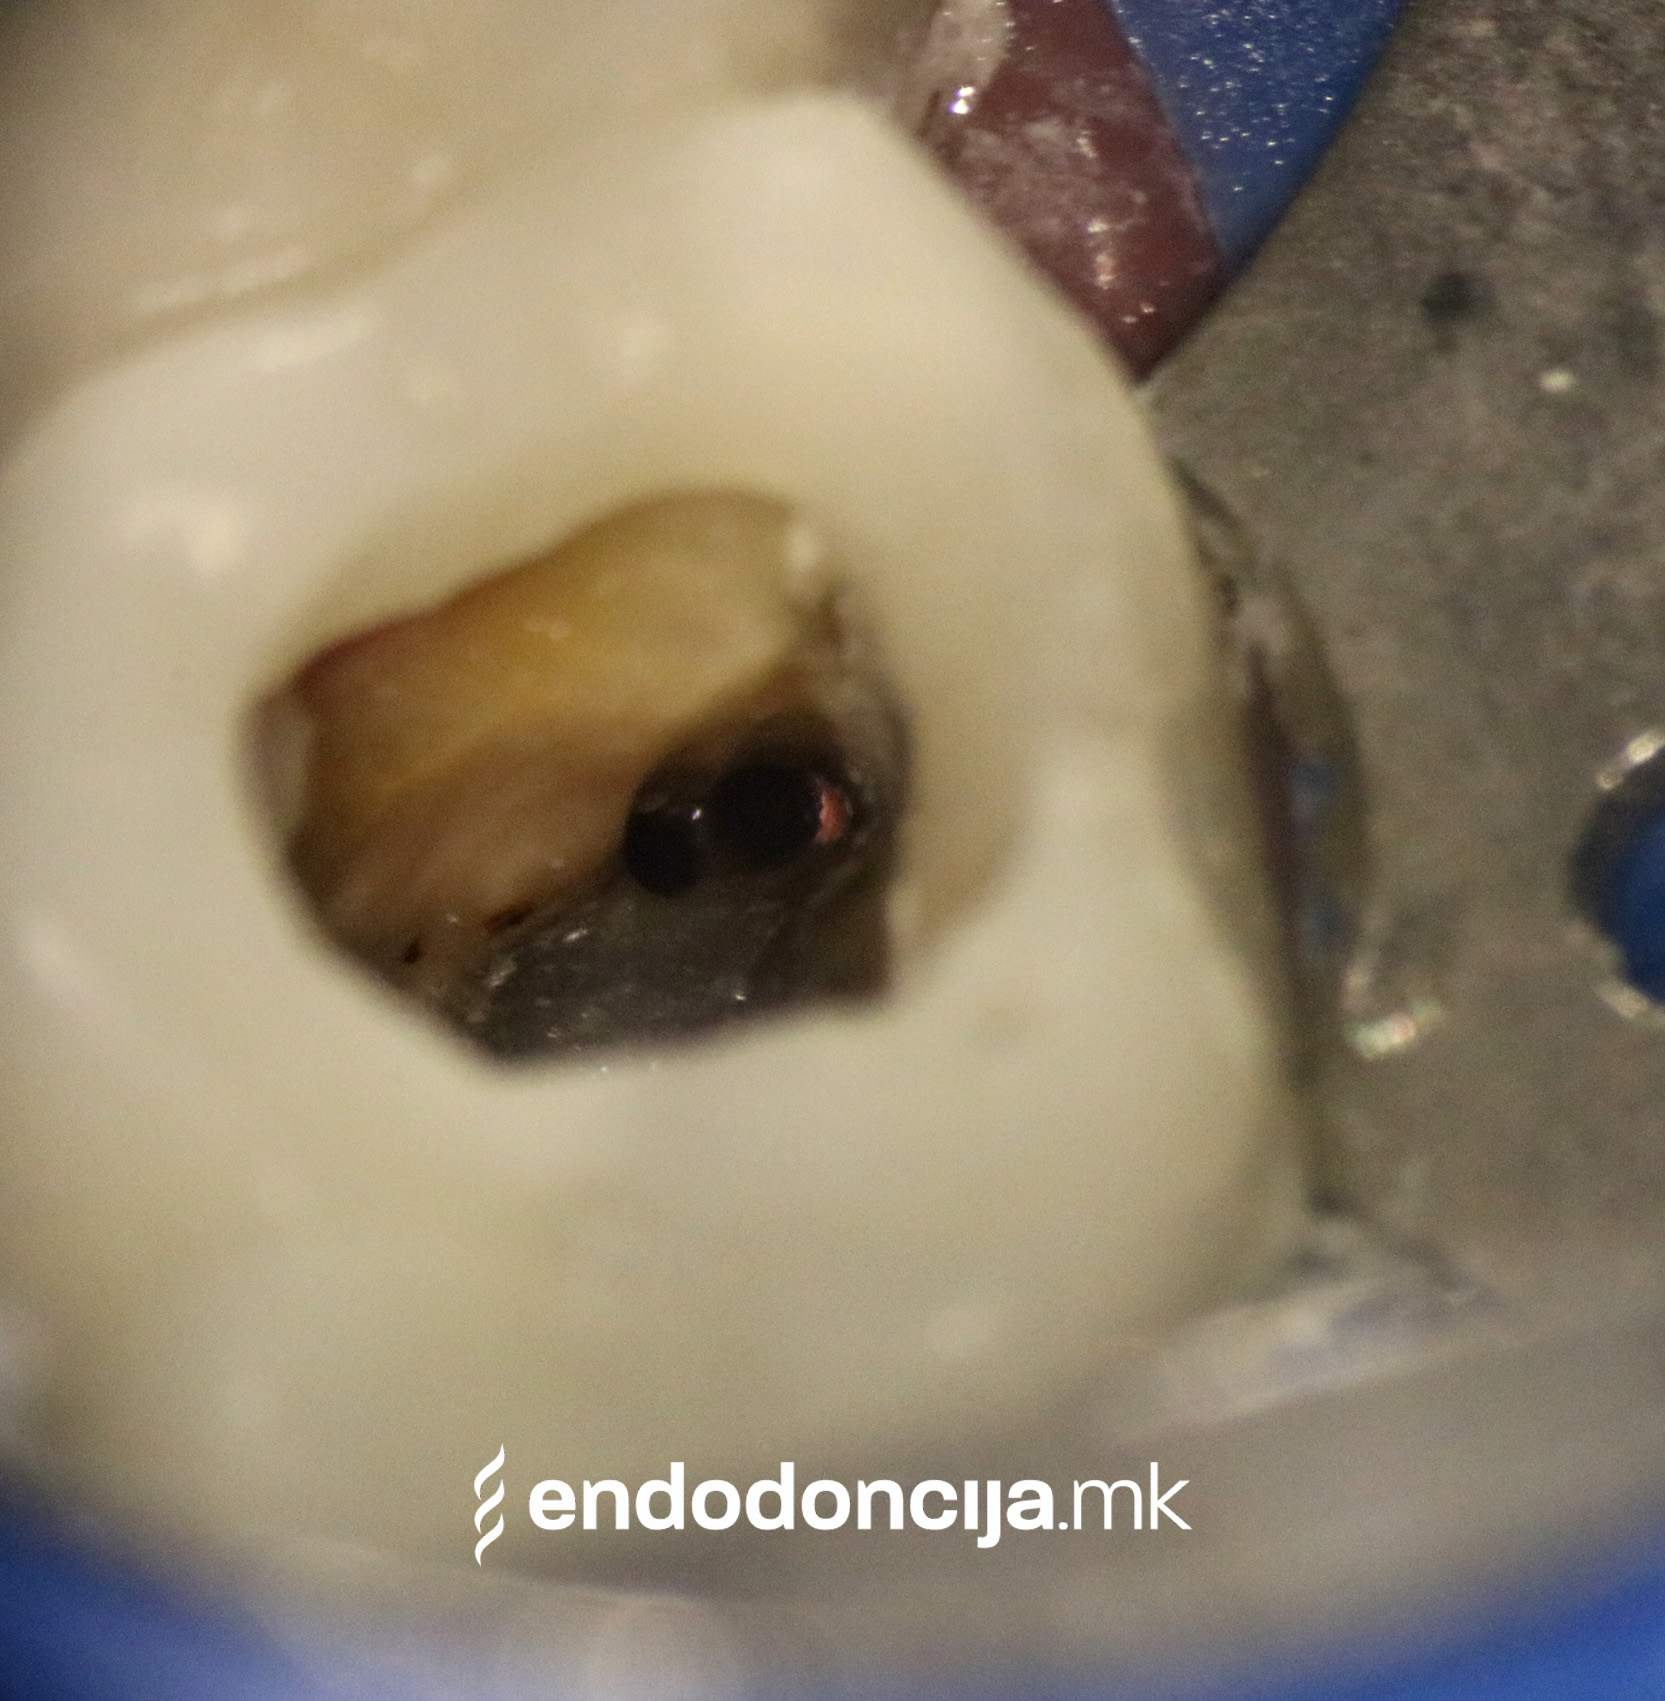

За време на претходните третмани, забот не само што бил ослабен со механички третман на коренскиот канал, туку и со поставување и закотвување на забното колче. Кога се ревидира третманот со коренскиот канал, овие колчиња треба да се отстранат колку што е можно повнимателно за да се задржи важната забна супстанција.

Она што е импресивно е прецизноста на микроскопските третмани. Дури и кога каналите се потешко достапни, може да се лоцираат и исчистат така што релапсите се со помала веројатност. Спротивно на тоа, скриените канали често остануваат неоткриени во конвенционалниот третман на коренскиот канал и затоа не можат да се чистат. Бактериите можат да се размножуваат таму без пречки и да предизвикаат воспаленија. Ова често останува незабележано со години додека не се појави забоболка, а со тоа и компликации.

Употребата на микроскоп исто така овозможува детектирање пукнатини или фрактури што може да предизвикаат болка или воспаление.